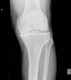

|Prompt diagnosis key in improving outcomes in psoriatic arthritis

25 Oct 2022

If left untreated psoriatic arthritis (PsA) can result in progressive, irreversible joint damage causing chronic pain and disability. It is a chronic, autoimmune inflammatory condition that can affect up to 30% of patients with psoriasis. PsA is a multisystem disease affecting other organs such as the eyes, gut and tendons. It is associated with multiple comorbidities such as diabetes mellitus, cardiovascular disease and metabolic syndrome. If PsA is suspected in primary care, routine blood tests should be requested to check for anaemia of chronic disease and raised inflammatory markers. Plain radiographs of hands and feet should be requested prior to referral, although classical changes do not occur early in the disease. If GPs suspect PsA, prompt referral is paramount. Patients should be referred if they have persistent joint symptoms, a positive screening questionnaire (PEST), joint swelling, dactylitis or enthesitis, and/or inflammatory back pain.